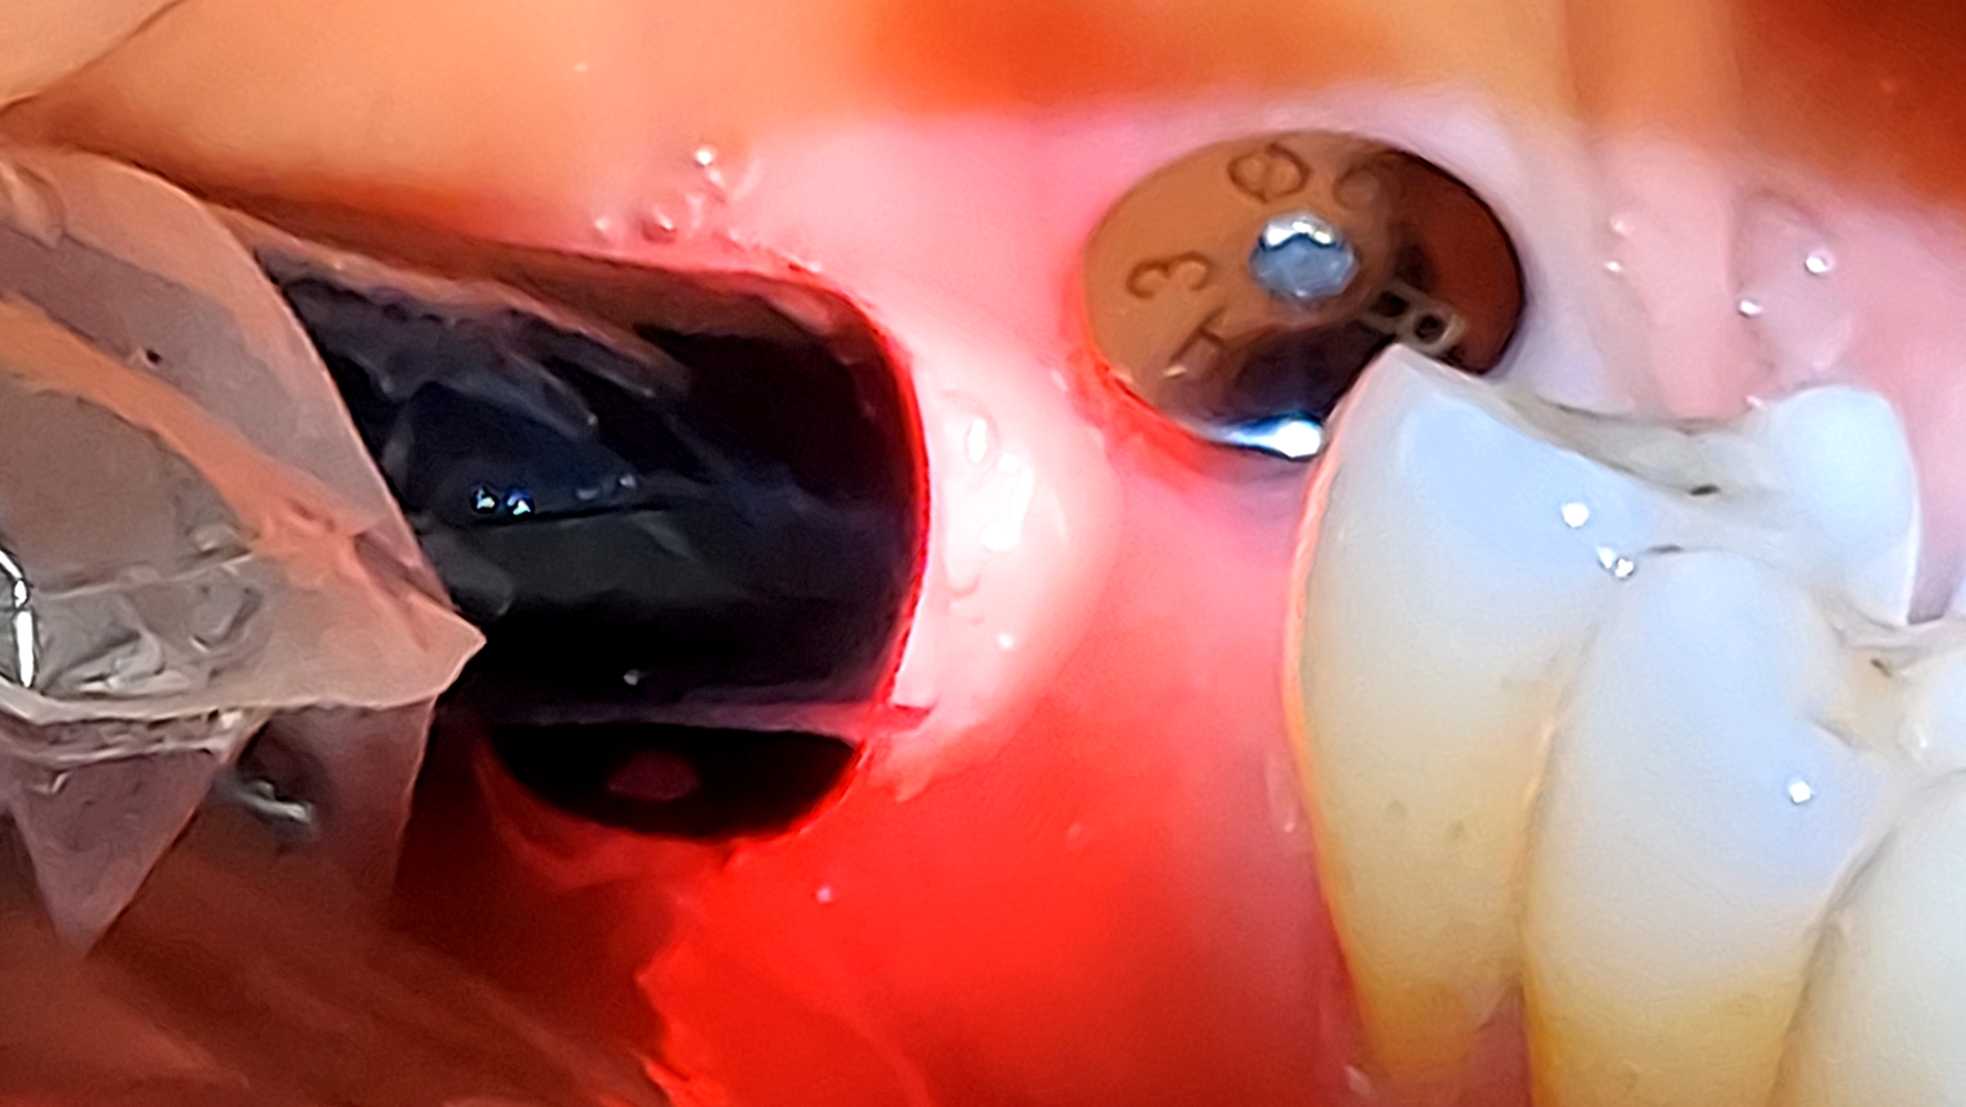

Approaching peri-implant conditions with laser precision

In recent decades, dental implants have emerged as a valuable tooth replacement option, offering favorable esthetic outcomes and long-term stability. Despite their high success rates, implants are subject to biological complications that compromise peri-implant tissues,1 peri-implant mucositis and peri-implantitis being two of the most common inflammatory conditions.2 Current epidemiological studies highlight the high prevalence of peri-implant mucositis, … Read more